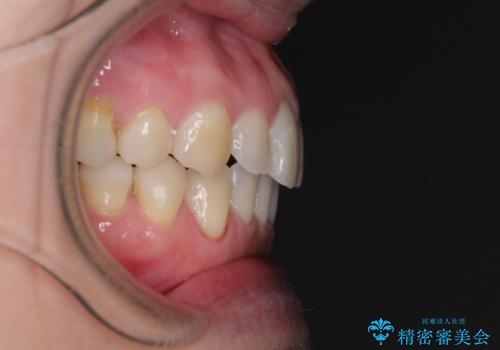

受け口傾向の歯並びをインビザラインで改善

- 受け口傾向でクロスバイトの前歯を治したいとのことで来院された患者様です。

下顎骨が若干左側に変位していたため、右側にアンカースクリューを使用し、積極的に移動させながらインビザラインにて矯正治療を行うこととしました。

インビザラインによる矯正治療は、受け口傾向の治療に非常に適した方法であり、事前にシミュレーションに沿って治療を進めることできます。

今回の治療では骨格的な偏位があったためアンカースクリューを使用し、より確率の高い治療を行うことができました。